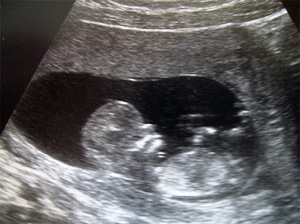

Ad otto settimane di gestazione, l’embrione in utero è lungo 3 cm, è ancora sprovvisto di occhi ed orecchie, ma è sufficiente che venga sfiorato per avere una reazione; ogni cellula è cullata e massaggiata dalle pareti uterine dal concepimento al parto,  ed  il benessere da adulti ha una grande connessione con questa esperienza prenatale.